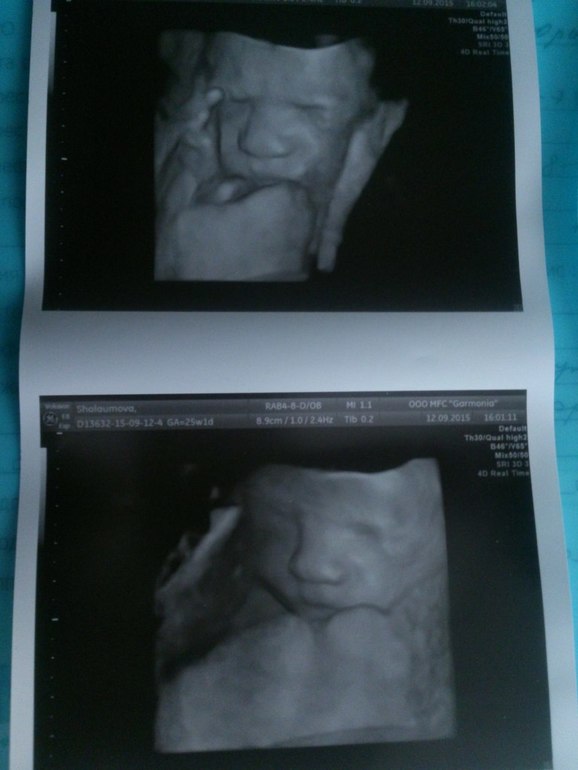

подтвердили мальчика в очередной раз) иногда врач включала режим 3Д-я видела все между ножек своими глазами))

он такой мииииилый!!! шевелился дрыгался)) если врач голову лицо тыкал-он хмурился и рукой закрывался, бедняга) еще рот открывал чего то)) все развито как надо все соответствует, воды, плацента в норме. сердце 145 уд в мин. вес 760 гр![]()